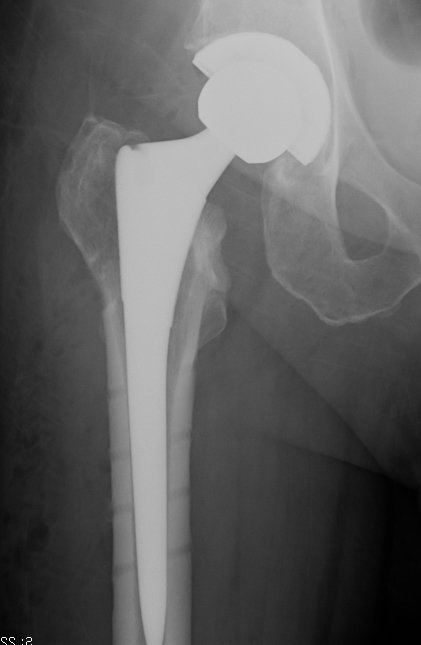

Hemiarthroplasty / Total hip replacement

Indications

- severe comminution

- salvage of failure of previous fixation

Technical

- may need calcar replacement

- may need greater trochanter fixation

THA Issues

A. Femoral component

- cement will come out screw holes

- Option 1: leave screws in laterally, and strip medially to insert small screws

- Option 2: use uncemented stem

B. Length of femoral stem

- should bypass distal screw hole by 2 cortical diameters

C. Calcar

- normal stem usually sufficient if LT healed back on

- otherwise may calcar replacing

D. Greater trochanter

- may need plate / cables to reduce